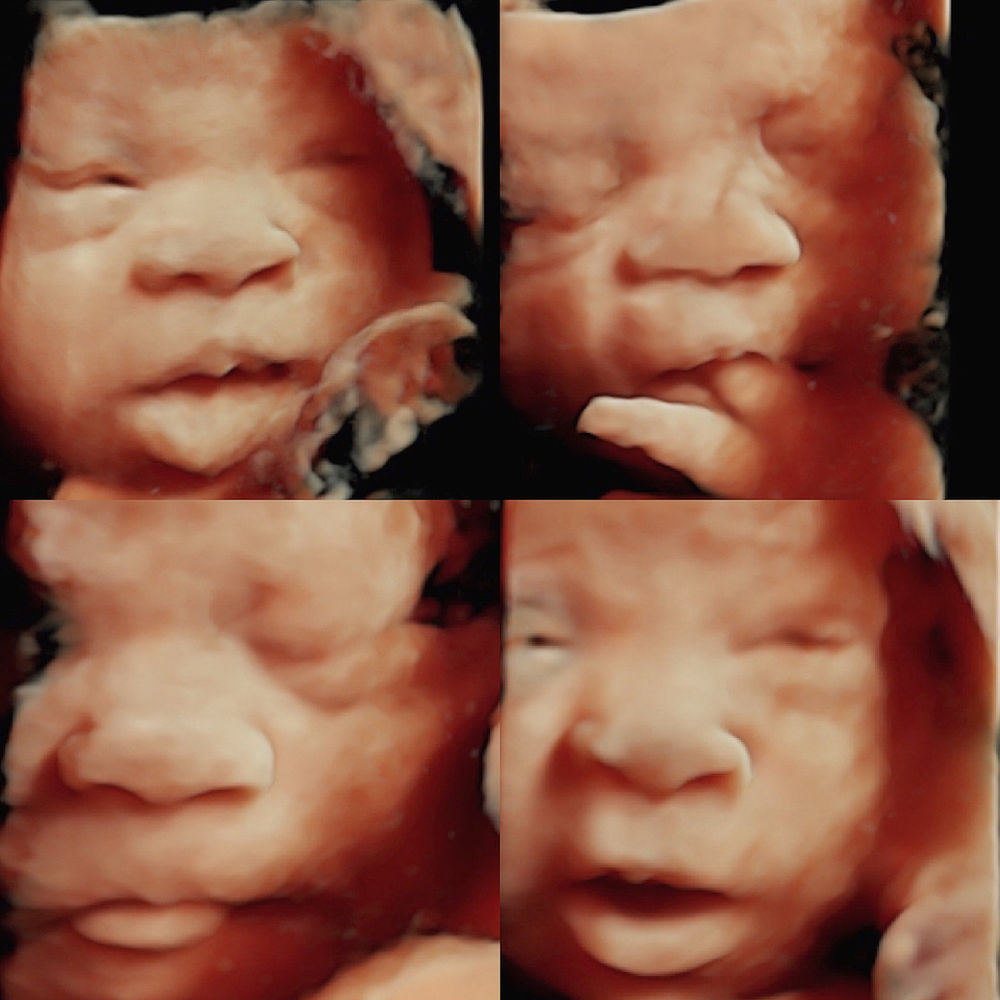

How To Get The Best 3D Ultrasound Pictures | 3D Baby Boutique

ultrasound 3d 4d.